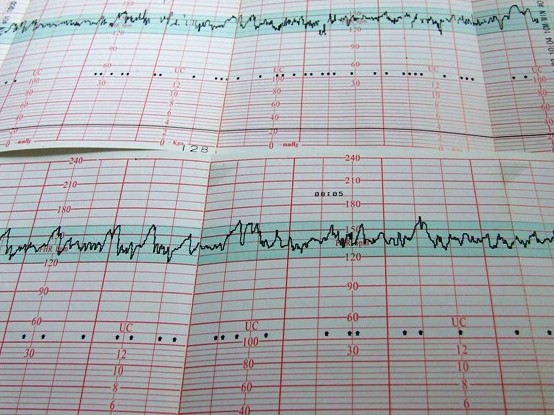

A lányunk CTG-i szaggatottak, lyukacsosak, a fiankéi pedig mindig folyamatosak, dimbes-dombosak.

A kislány szíve a jobb medencecsontomnál dobog, így nagyon kényelmetlen testhelyzetben tudom a koronggal befogni, ráadásul csak a jobb oldalamon fekhetek, mert ha megfordulnék, nem látnám a képernyőt (a hangot kikapcsoljuk, ne legyen a szobatársak számára zavaró). A férjem szerint a babák ebben a korban kilencven százalékban alszanak, de a miéink továbbra is igen mocorgósak, főként főétkezések után és este meg éjjel, ahogy korábban is. Férjem imádja megfogni a hasam, itt van apuci, súgja nekik, miután megpuszilt, és nézi a bőrömön a domborzati változásokat, hogyan nyújtózkodnak, másznak odébb, tapogatnak, rugdalóznak. Szereti felfedezni a mozdulataikat. Olyan szépen nézi hasam hullámzását és beszél hozzájuk!

Egyes napokon sok minden történik, de előfordul, hogy csak a napokat számolom. Tartalmas kórházi életemről egyszer így számoltam be, arra reagálva, hogy a rokonságnak repül az idő, nekem bezzeg mennyire unalmas lehet: „Dehogy unatkozom meg nezem a plafont! Szamtalan konyvet elolvastam, megneztem sok filmet, le kell heti egyszer lifteznem uktrahangra, ennem is kell, a kanalat is alig birom megemelni.... Mindenki gyereket agyon kell dicserni, meghallgatni a sztorikat, kinek van lelegezteton, kakil-e, pisil-e, milyen babacuccokat vettek. Naponta hajnali otkor kapom a verhigitot, minden szerdan pisiteszt, csutortok hajnali otkor vervetel, fel nyolckor naponta vizit. Utana egy ora ctg (szivhangmeres). Delutan latogatas... a babak nyomjak a hugyholyagom, surun kell vecere jarnom. Naponta haromszor gyogyszereket kell bevennem. Alig gyozom. Ezt nevezitek ti unatkozasnak?!:)”